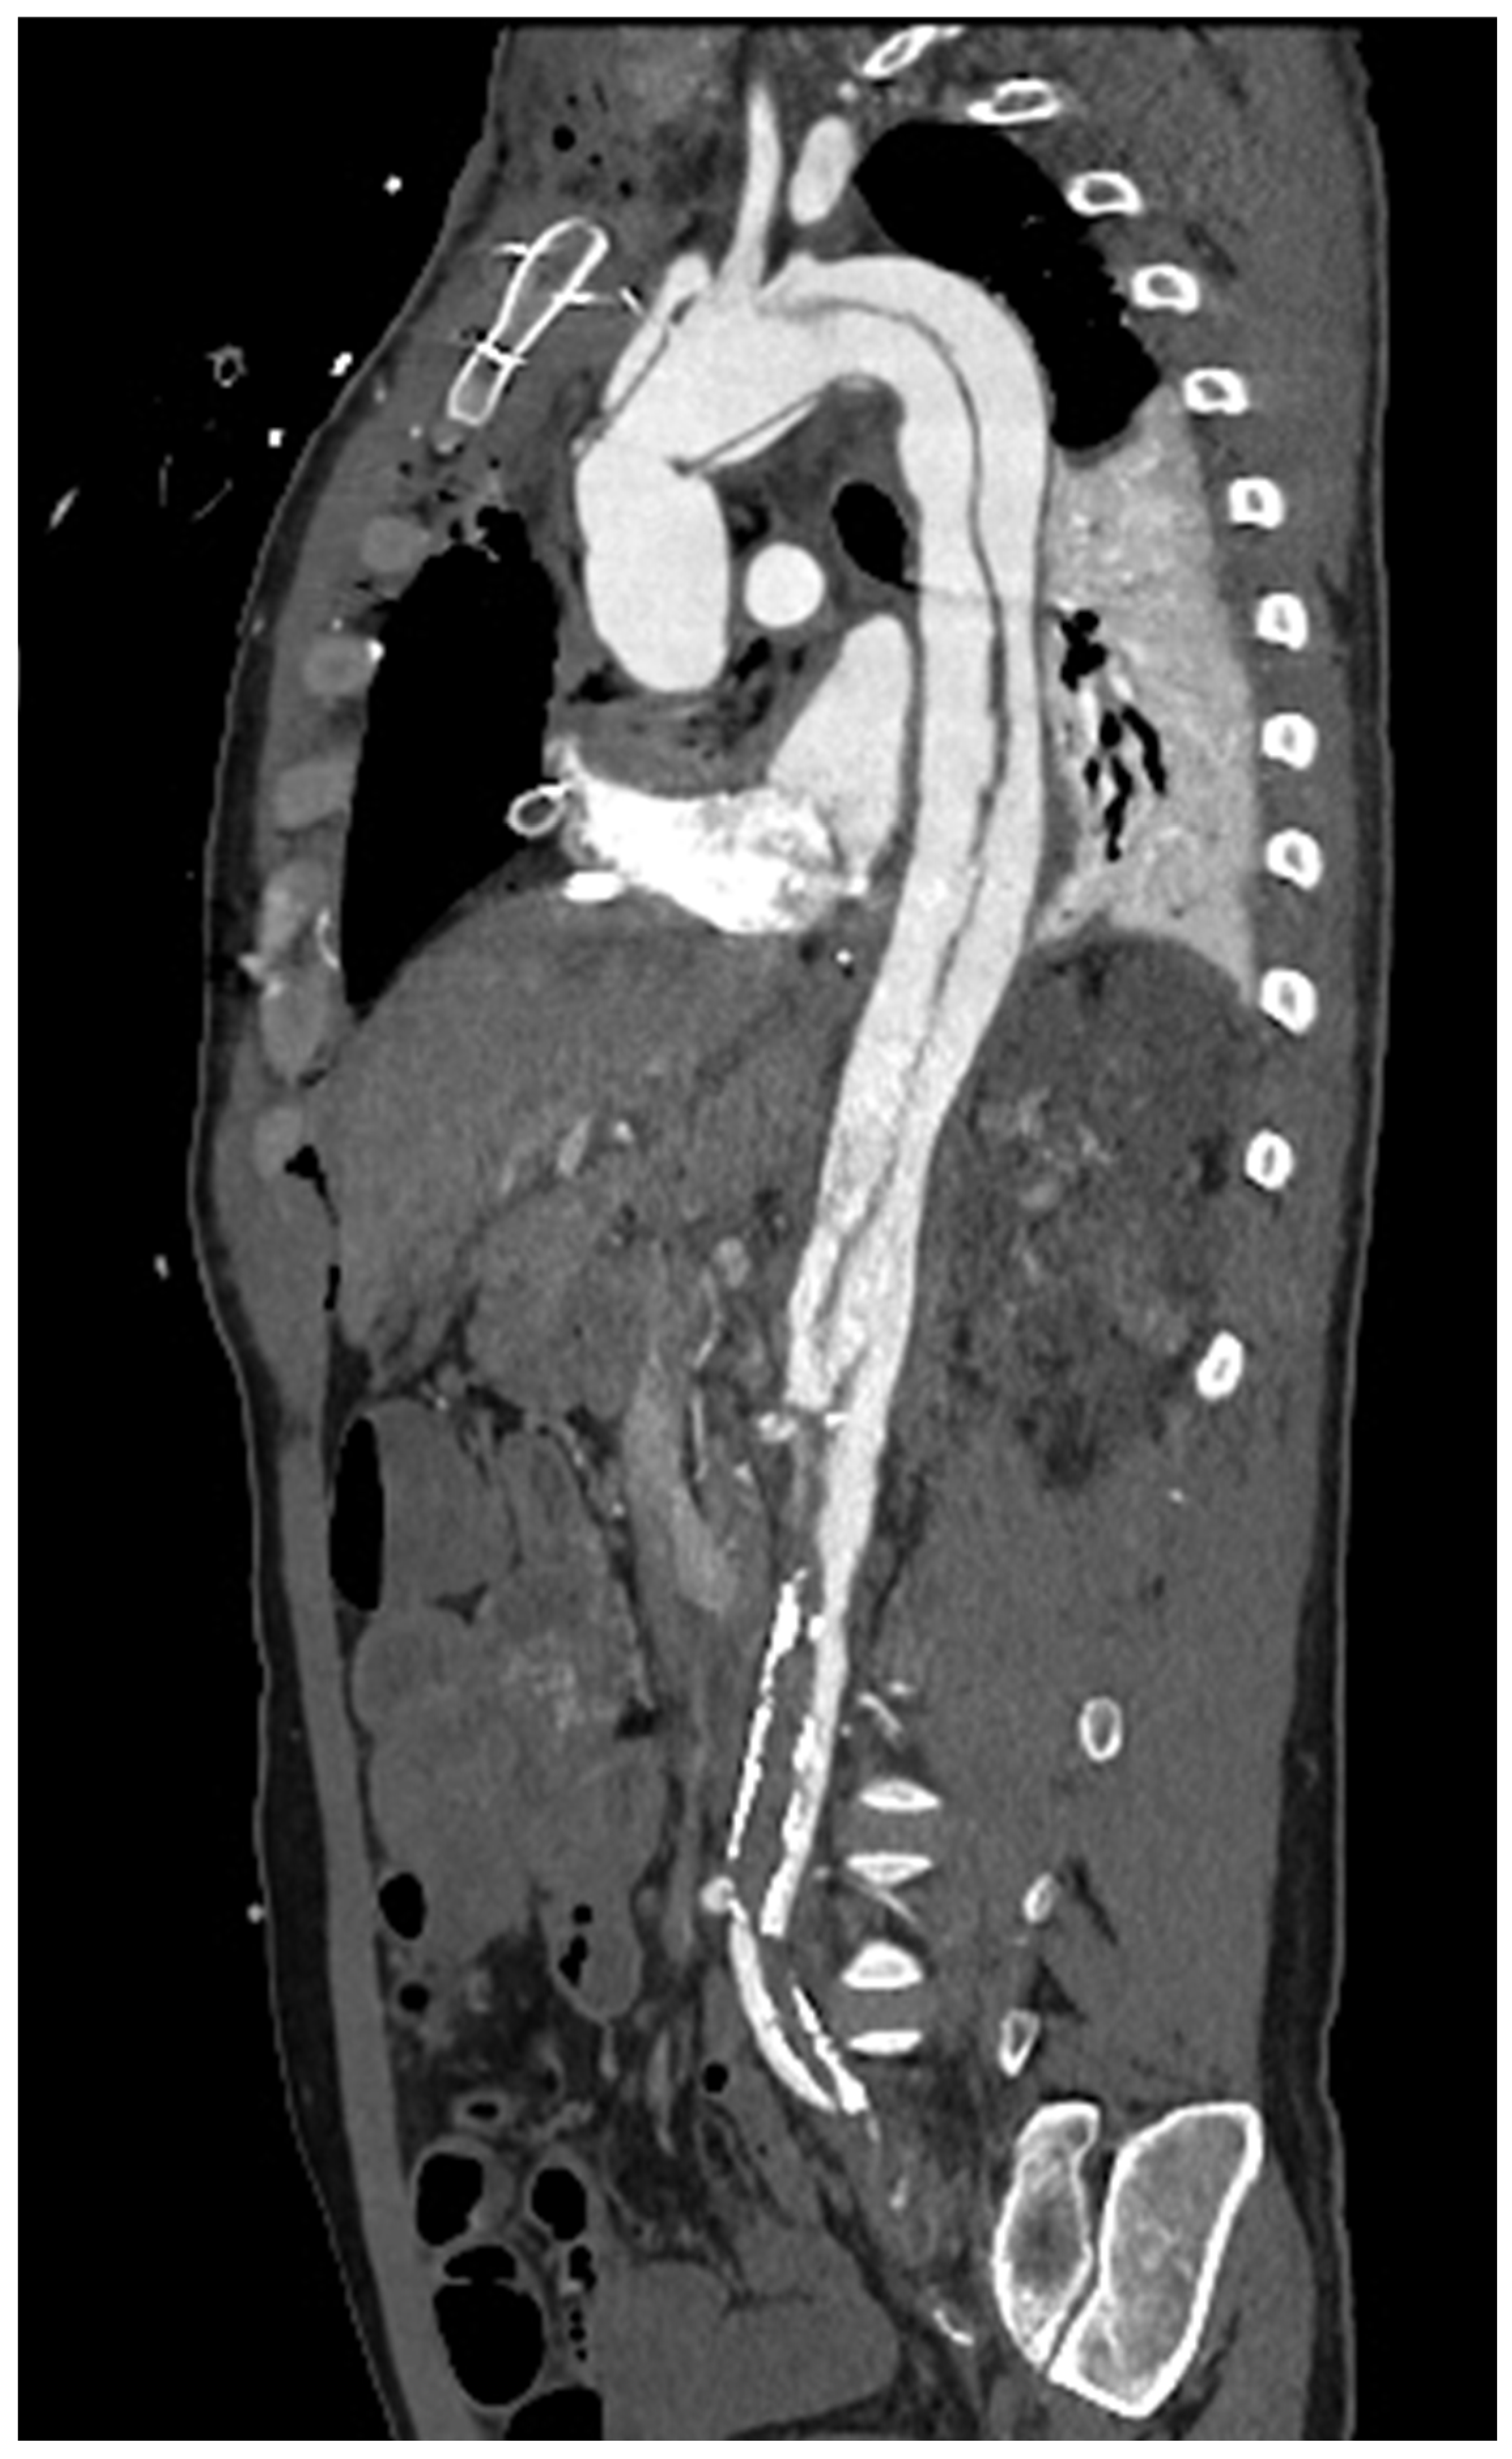

2. Vascular Imaging

- Wielandner, A.; Beitzke, D.; Schernthaner, R.; Wolf, F.; Langenberger, C.; Stadler, A.; Loewe, C. Is ECG triggering for motion artefact reduction in dual-source CT angiography of the ascending aorta still required with high-pitch scanning? The role of ECG-gating in high-pitch dual-source CT of the ascending aorta. Br. J. Radiol. 2016, 89, 20160174. [Google Scholar] [CrossRef]

- Guo, Y.; Chen, X.; Lin, X.; Chen, L.; Shu, J.; Pang, P.; Cheng, J.; Xu, M.; Sun, Z. Non-contrast CT-based radiomic signature for screening thoracic aortic dissections: A multicenter study. Eur. Radiol. 2021, 31, 7067–7076. [Google Scholar] [CrossRef]

- Wang, Y.; Xiong, F.; Leach, J.; Kao, E.; Tian, B.; Zhu, C.; Zhang, Y.; Hope, M.; Saloner, D.; Mitsouras, D. Contrast-enhanced CT radiomics improves the prediction of abdominal aortic aneurysm progression. Eur. Radiol. 2023, 33, 3444–3454. [Google Scholar] [CrossRef] [PubMed]